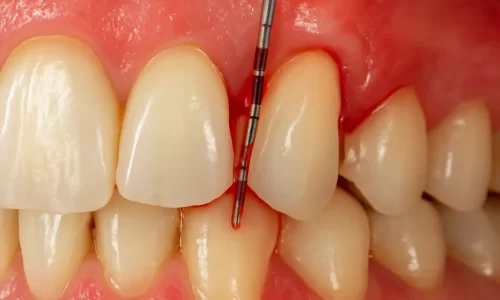

- Clae 2 - Clasificacion diagnostico y pronostico periodontaldiscusión exhaustiva sobre la enfermedad periodontal, abarcando su clasificación, diagnóstico y pronóstico. Se enfatiza la evolución del entendimiento de la enfermedad, pasando de ser considerada una afección oral a una enfermedad sistémica con manifestaciones orales, influenciada por factores locales, sistémicos, genéticos y ambientales. Se detallan métodos diagnósticos como el periodontograma y el uso de reveladores de biopelícula, resaltando la importancia de una historia clínica completa y la identificación de factores de riesgo. Finalmente, se exploran diversos sistemas de pronóstico, tanto del paciente como de los dientes, subrayando la necesidad de un tratamiento integral y un mantenimiento continuo para asegurar la salud bucal a largo plazo.3